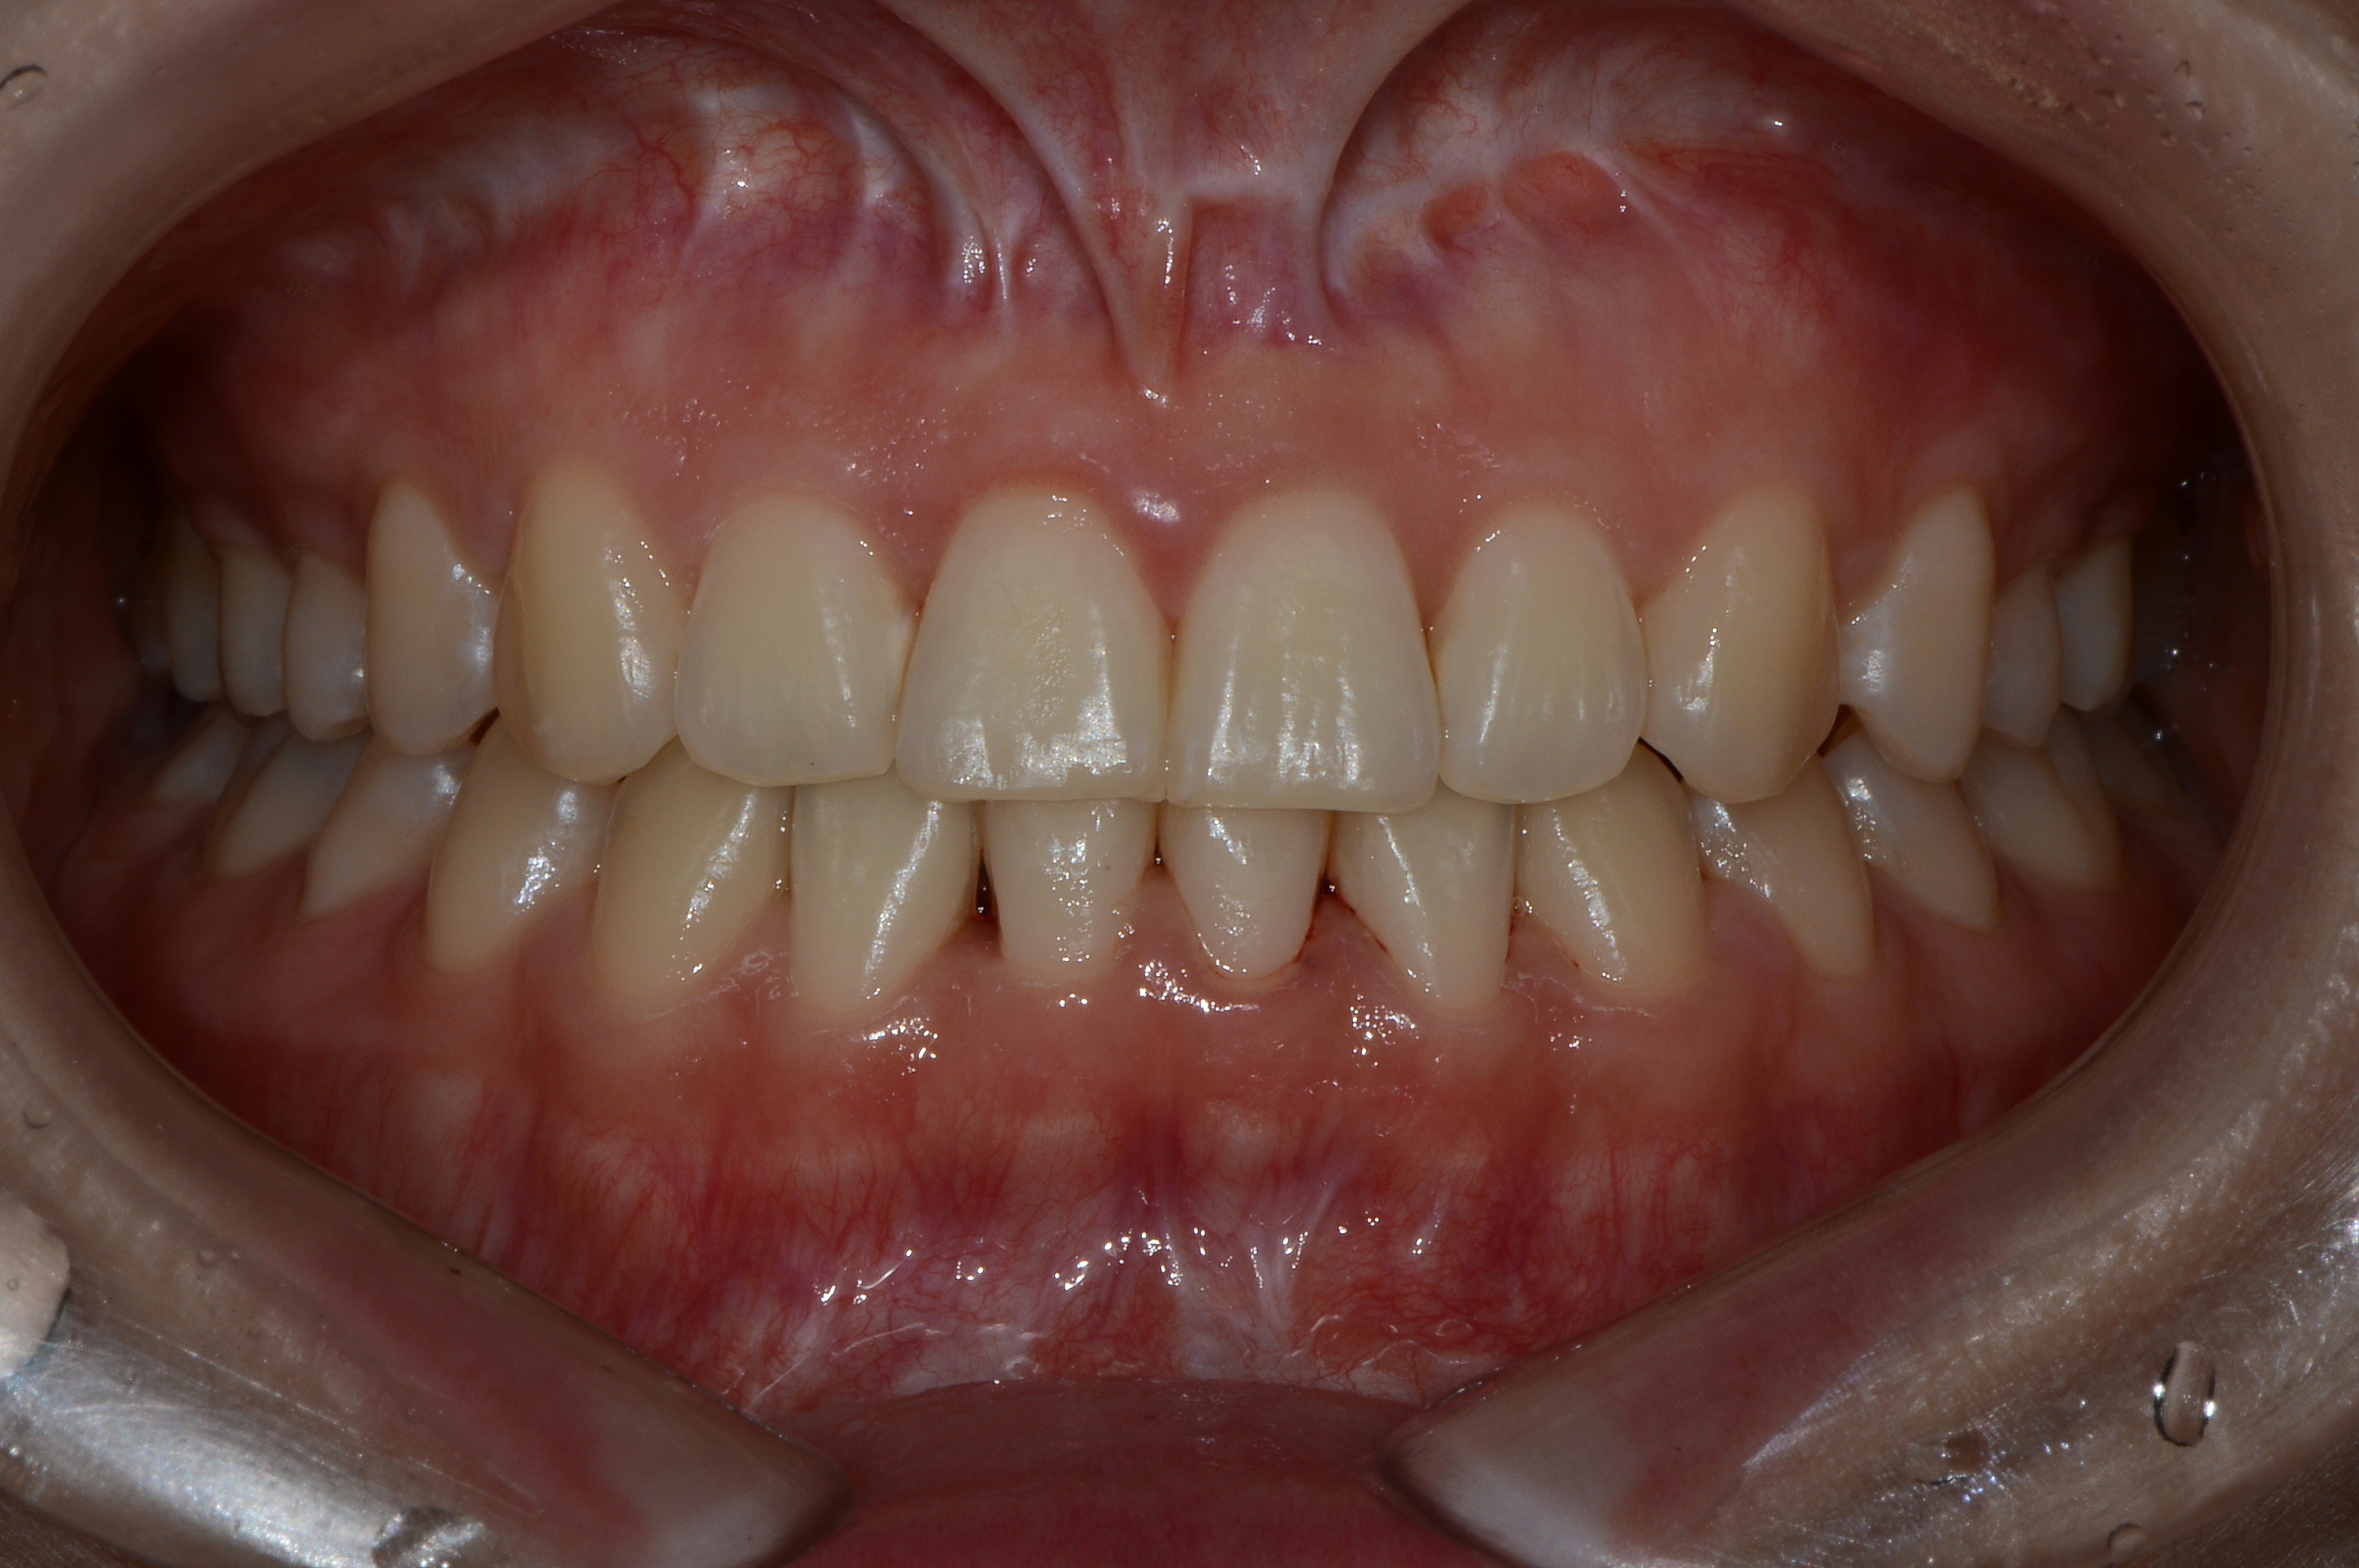

치료 전 사진입니다.